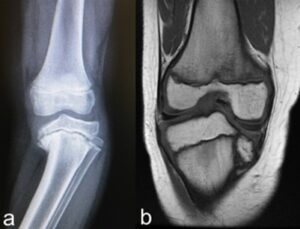

To decide which surgical procedure to perform to correct Blount’s disease, it is necessary to consider the deformity present in the specific case. In fact, the progression of the pathology determines different anatomo-pathological conditions, for which it is necessary to adapt the procedure to the specific problem. Typical findings are: deformation of the articular surface of the tibia (the internal part is lowered compared to the external one), worsening varus deviation, deformation of the distal femur, shortening of the limb, etc.

The surgeon will request specific diagnostic tests to perform this evaluation (X-ray, MRI, etc.)